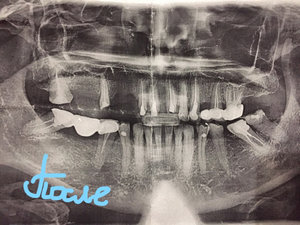

Летом мне установили металлокерамические коронки. Но в связи неправильной обточкой и конструкцией мне пришлось их снять из-за воспаления десны. Имеется панорамный снимок челюсти. И так как после консультации ряда стоматологов мнения не совпали. Хочется узнать состояние десен и пломбирование каналов?

Комментарий №175144 Комментарий №175144

• Состояние десны по ортопантомограмме оценить невозможно, только костную ткань. 45-е, 47-е зубы лучше оценить на КТ, так как каналы запломбированы не до верхушки корня.